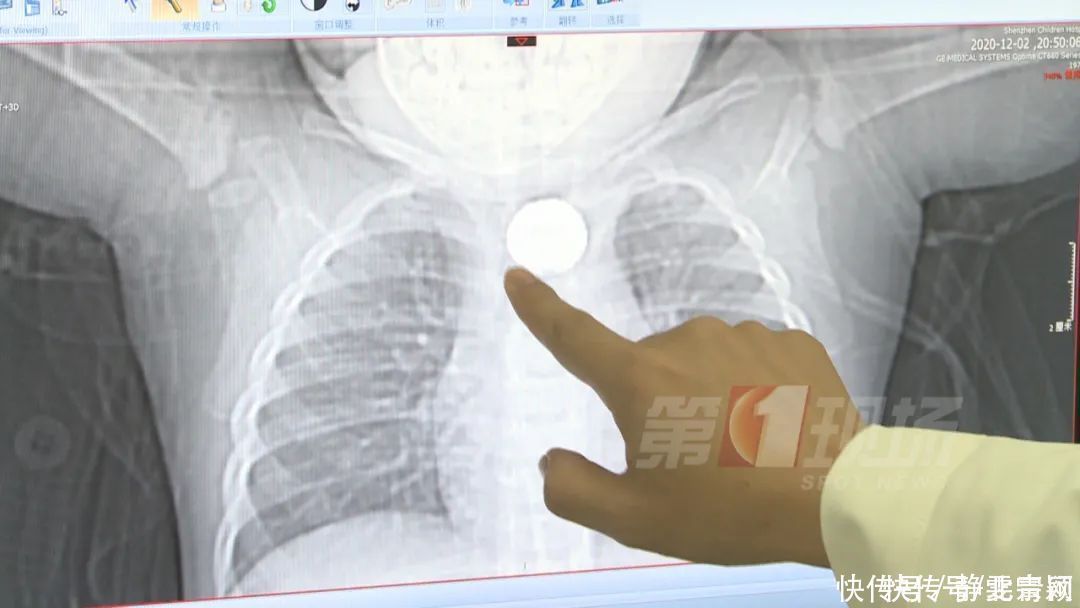

随后王先生再次送孩子到医院拍片

才发现是异物卡在了食道

吴泽斌 深圳市儿童医院耳鼻喉科副主任医师

我们医生一看这个异物,跟我们普通的硬币不一样。它的密度不是非常的均匀,边缘有一些蚕丝一样的密度不均匀的影子。所以我们首先高度怀疑它是纽扣电池的食管异物。之后我们马上给他安排了绿色通道,进行急诊手术。